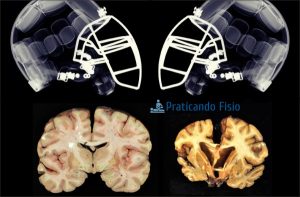

As concussões frequentes em jogadores de Futebol americano podem ser a principal causa ETC – Encefalopatia Traumática Crônica, uma condição de neurodegeneração progressiva, causada por sucessivos golpes na cabeça, um caso diagnosticado recentemente com ETC Grave foi o do jogador Aaron Hernandez, Ex-Jogador do New England Patriots, time que estará na final do SuperBowl neste domingo dia 04 de fevereiro.

Para saber mais sobre ETC vale a pena assistir ao Filme The Concussion (2015) com Will Smith, o filme trata sobre o patologista forense, Dr. Bennet Omalu, que tenta conscientizar a opinião pública sobre a encefalopatia traumática crônica, uma doença que causa trauma cerebral em jogadores de futebol americano, resultado de concussões repetidas na cabeça.

Para saber mais sobre ETC vale a pena assistir ao Filme The Concussion (2015) com Will Smith, o filme trata sobre o patologista forense, Dr. Bennet Omalu, que tenta conscientizar a opinião pública sobre a encefalopatia traumática crônica, uma doença que causa trauma cerebral em jogadores de futebol americano, resultado de concussões repetidas na cabeça.